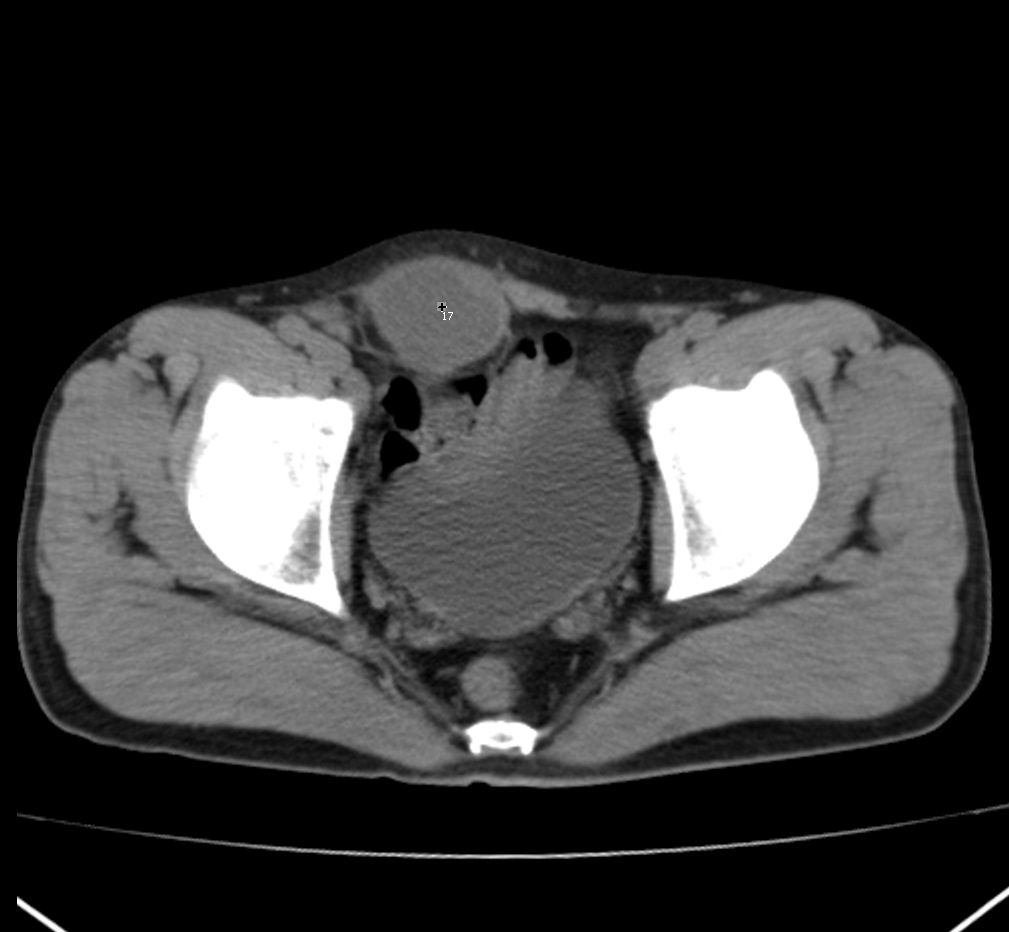

定位:右腹直肌鞘下部

病灶特点:分界清,边缘光整,囊性密度,病灶成长椭圆形,病灶处腹直肌受压萎缩,病灶与膀胱处有相似密度管状灶(该征象因肠道未作准备,不能确切)

右腹直肌腱鞘来源,韧带样纤维瘤可能性大,病变有侵袭性,右侧耻骨联合有骨质缺损。

前腹壁肿块,囊性变,右侧耻骨联合有骨质缺损。

右腹直肌腱鞘来源,耻骨联合有骨质缺损,考虑神经源性肿瘤